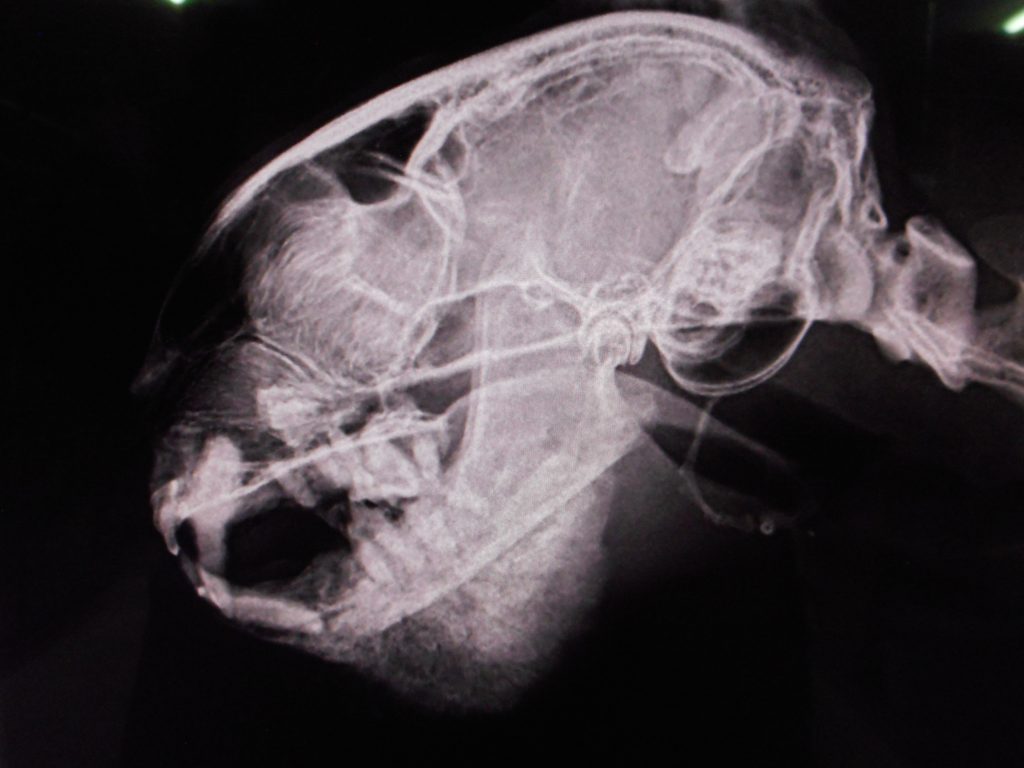

硬く腫れている、高齢猫が来院

歯周病?

それにしては硬すぎる

暫定診断:骨腫瘍

猫の顔面の骨腫瘍は比較的多い病気です

その一部を切除して病理組織学的検査に提出しなければその正体がわかりません

今後は生検を考慮しつつ、まずは抗生剤から始まります

Swelling of the lower jaw

and so old cat

Possible malignant tumor